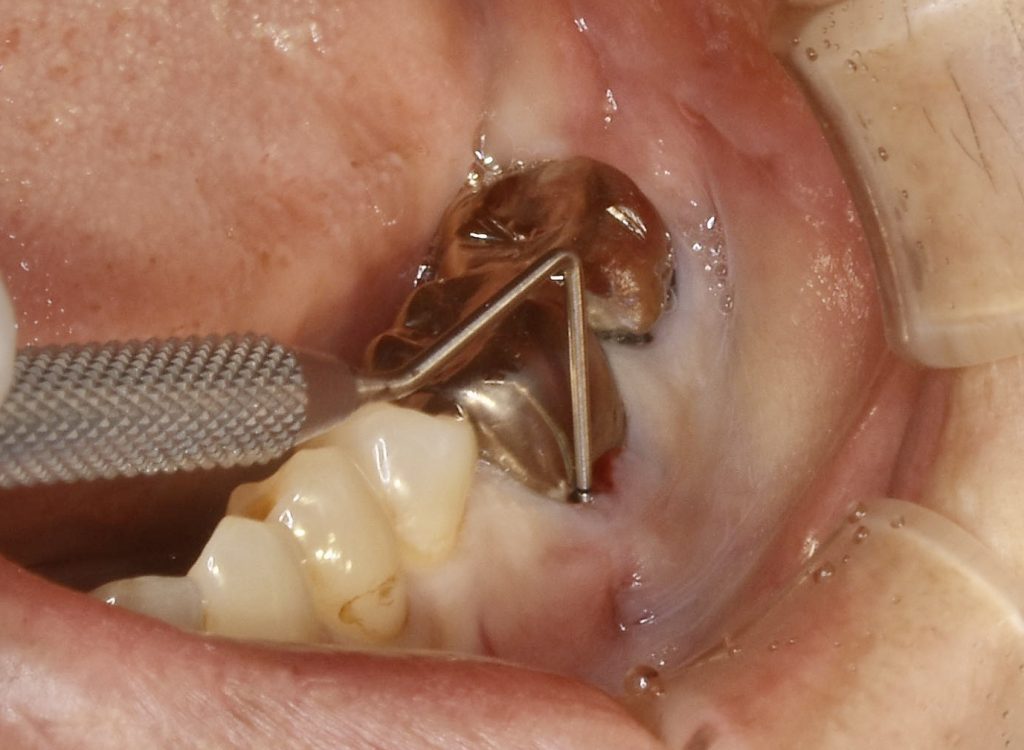

歯根破折を起こし、周囲の骨が炎症を起こしていました。

骨の再生のみならず、歯肉も不足していた為、歯肉移植を行いメンテナンスしやすい環境を整えました。